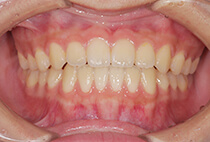

治療前

治療後

八重歯の見た目が気になってご来院されましたが、実は顎の痛みや開口障害など、顎関節症の症状もありました。

そのため、かみ合わせと顎関節症の治療を同時に行ったにもかかわらず、2年間で治療が終了。

かみ合わせが整い咬筋の過緊張も改善しました。咬筋の肥大も治ってフェイスラインがすっきりしました。

最終的には美しい歯並びと、安定した痛みのないかみ合わせが実現しました。

しっかり前歯を下げるために、インプラントアンカーを使用してコントロールしました。

かみ合わせが整うと咬筋の過緊張が改善。

過緊張による筋肉肥大も改善しフェイスラインもすっきりしました。